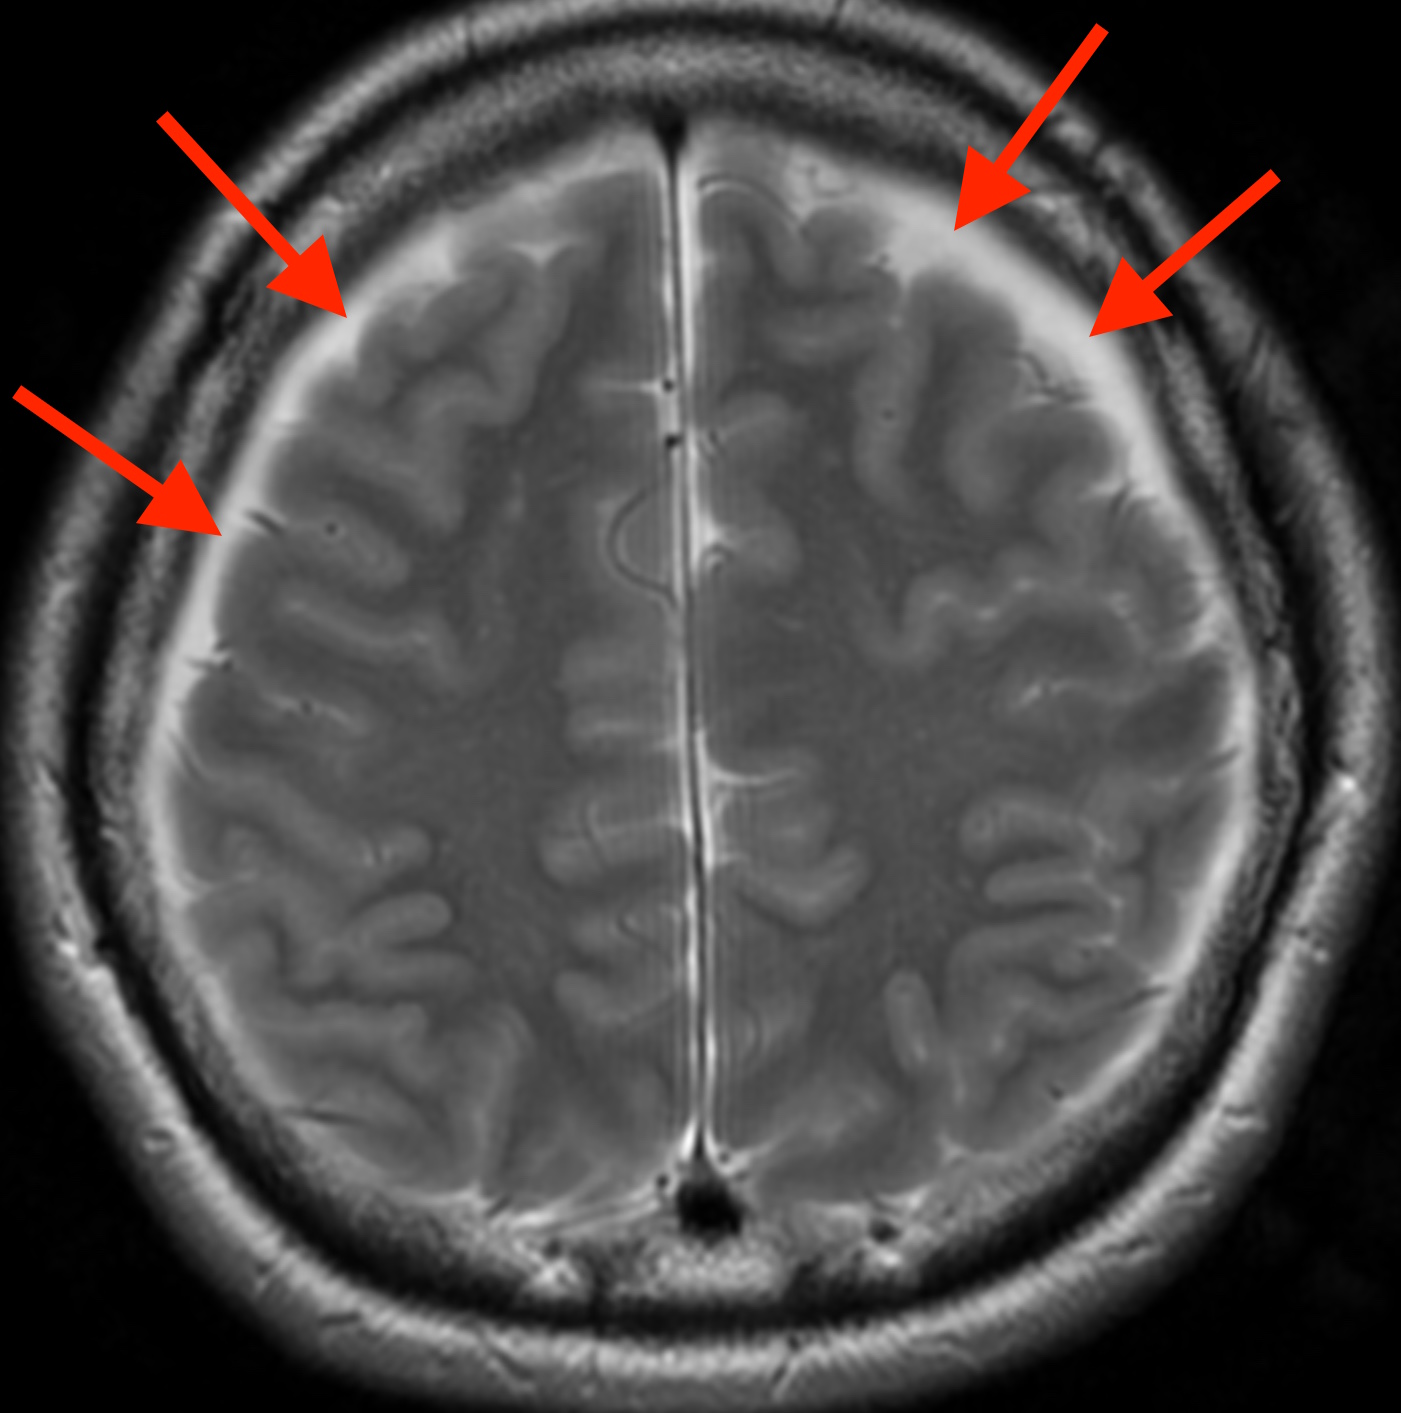

脳脊髄液減少症の軸位断MRI

脳の周りにすき間(赤矢印)が見えています。このすき間の部分は血液が貯まったもので、「慢性硬膜下血腫」と言います。